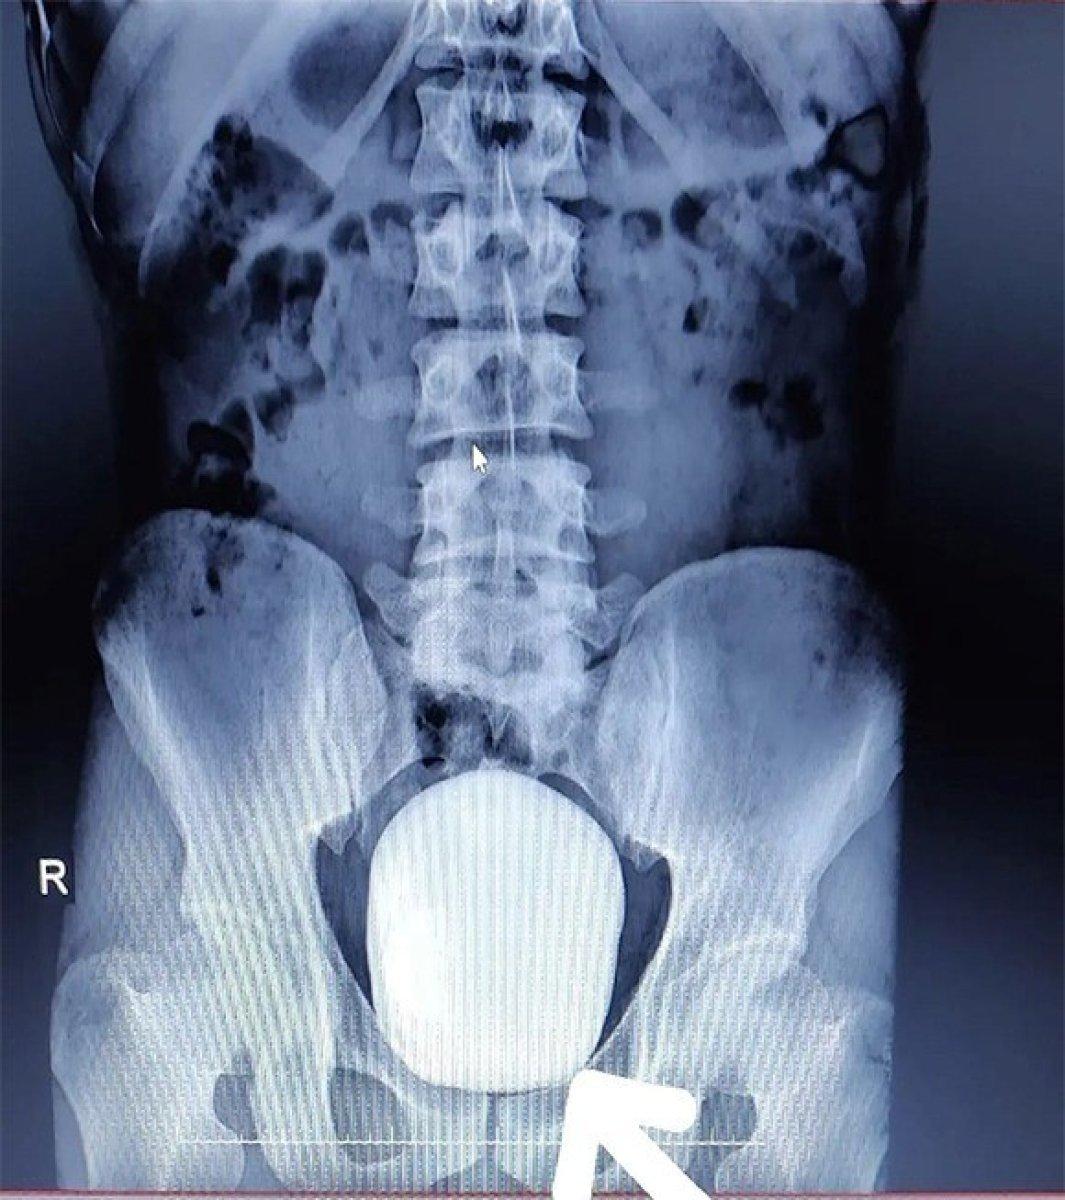

Karaman’da yaşayan 27 yaşındaki Barış Yıldız isimli hasta, idrar yaparken yanma şikayeti ile Karaman Eğitim ve Araştırma Hastanesine başvurdu. Çekilen röntgeninde hastanın mesanesinde 2 adet büyük çapta taş tespit edildi.

İHA'nın haberine göre; başarılı geçen ameliyatla ilgili değerlendirmelerde bulunan Doç. Dr. Güven Erbay, “Hastanemize idrarda yanma şikayeti ile başvurdu. Yapılan tetkik ve görüntüleme sonucunda mesanesinde devasa bir taş olduğu gördük. Bunun üzerine ameliyat kararı aldık ve açık ameliyatla bu taşı aldık. Normalde mesane taşı yaşlı hastalarda ve prostatı olanlarda oluşur. Genç yaştakilerde pek beklediğimiz bir durum değildir. Başarılı geçen ameliyatın sonunda hastamızın mesanesinden 15 ve 5 santim boyutunda 2 tane taş çıkardık. Hastamızın sağlığı gayet iyi durumdadır. Şu ana kadar bilinen ve bizim de bildiğimiz kadarıyla bir hastadan çıkarılan taş bin 900 gram ağırlığındaydı. Bizim çıkardığımız 2 taşın ağırlığını ölçtüğümüzde bin 50 gram geldi. Bizim bildiğimiz üzere bu çıkarılan taşın Türkiye sınırlarında şimdiye kadar mesaneden çıkarılan en büyük taş olduğunu düşünmekteyiz" dedi.